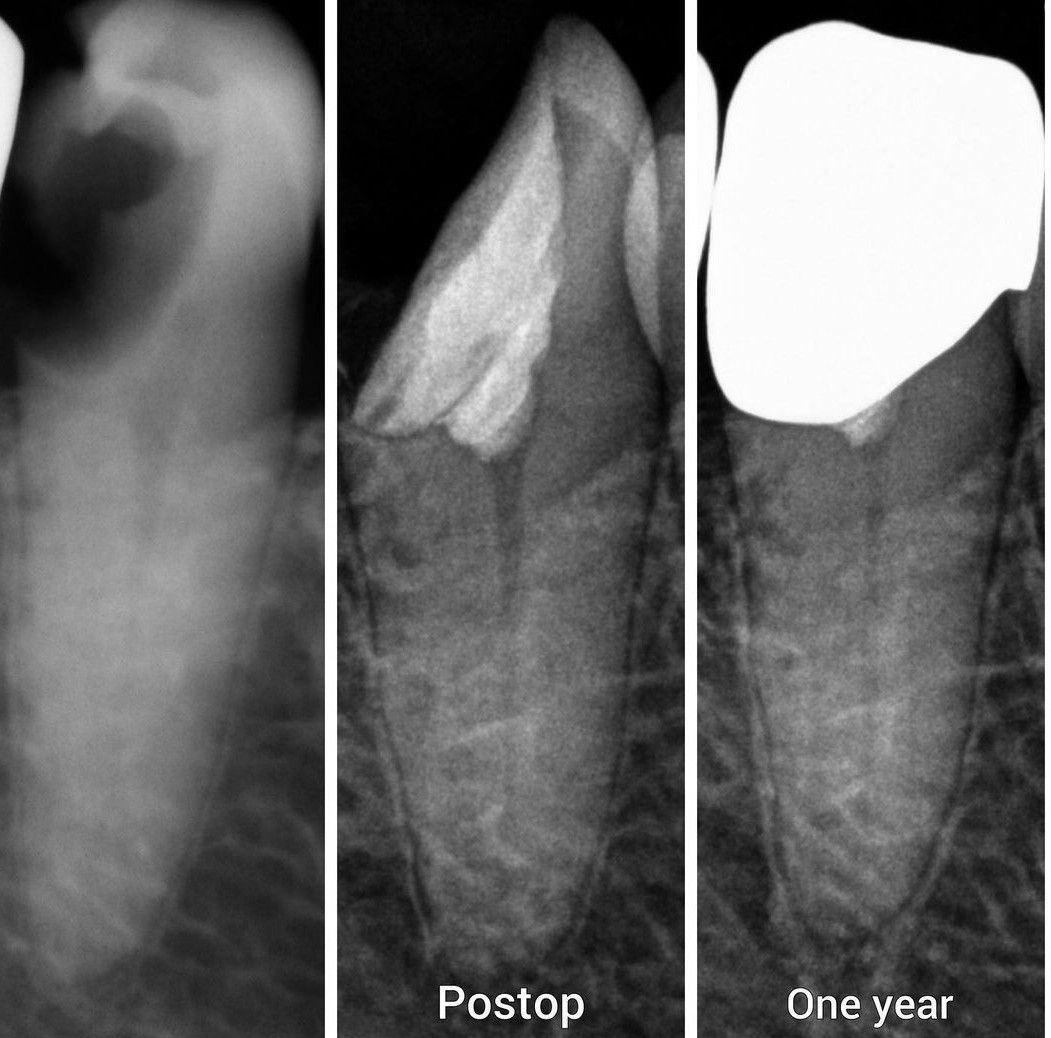

One Year Post-op

One year post-op after vital pulp therapy.